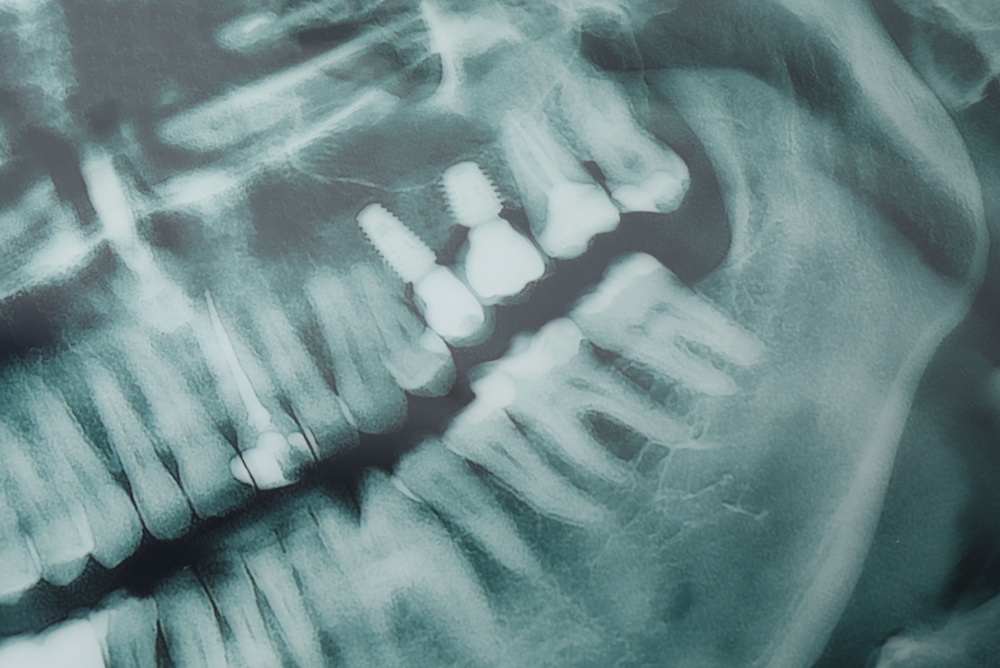

Your provider will review health history, take X-rays or 3D scans, and create a digital plan. This step identifies bone levels, nerve positions, and the best implant size and angle.